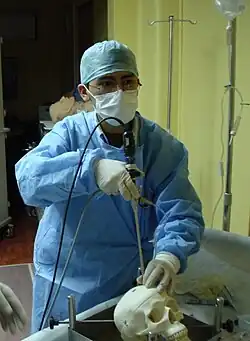

Medizinische Endoskopie

Medizinische Endoskope haben die Untersuchung des Magen-Darmtraktes, der Lunge und auch der Gebärmutter revolutioniert. Sogar die ableitenden Tränenwege können endoskopisch untersucht werden.

Eine medizinische Endoskopieeinheit umfasst über die unter Basis beschriebenen Komponenten hinaus:

- zwingend

- einen Luftinsufflator oder eine Gaspumpe zum dosierten Aufblasen von Hohlorganen oder Körperhöhlen (Bauchhöhle), bei denen sonst die Wände auf die Optik fallen oder Details in Falten verdeckt würden.

Im einfachsten Fall ist dies ein Gummiballon mit Ventil (bei der Rektoskopie, siehe unten), der von Hand betätigt wird. Bei flexiblen Endoskopien (Gastroskopie beispielsweise) wird eine drucklimitierte Pumpe verwendet und das Einblasen der Luft vom Endoskopiker mittels Fingerventilen bewirkt. Bei der Bauchhöhlenspiegelung hingegen benutzt man mengen- und drucklimitiert geregelte Automaten und zur Vermeidung einer Luftembolie wird CO2-Gas anstelle von Luft eingeblasen. - einen Irrigator: im einfachsten Falle eine mit Kochsalzlösung gefüllte Spritze oder Infusionsflasche

- eine Absaugpumpe für Schleim und andere unerwünschte flüssige Inhalte der Hohlorgane

- bedarfsweise

- einen Koagulator zur Blutstillung

- flexible Werkzeuge. Sie werden über Arbeitskanäle eingebracht.

- Greif- oder Schneidwerkzeugen zwecks Gewinnung von Gewebeproben

- Kanülen zur Injektion

- Drahtelektroden zur Koagulation mit elektrischem Strom.

Heutzutage wird, vor allem unter stationären Bedingungen, das Bild nicht mehr direkt mit dem Auge (weder am starren Rohrendoskop, noch am Okular des flexiblen Endoskops) betrachtet, sondern an einem oder mehreren modernen Monitoren, die die Farbinformation möglichst wenig verfälschen, und die die Arbeit und das Lehren (Kibitzen) ohne Qualitätsverlust bei Tageslicht ermöglichen. Dadurch eröffnet sich zusätzlich auch die Möglichkeit der Aufzeichnung auf Videoträger oder eine Übertragung in Hörsäle.

Vorbereitung in der medizinischen Endoskopie

Bei den meisten endoskopischen Untersuchungen erfolgt für den Betroffenen zur Erleichterung eine Prämedikation, das heißt, es wird ein Beruhigungsmittel, zum Beispiel Midazolam, oder das Narkosemittel Propofol gegeben.